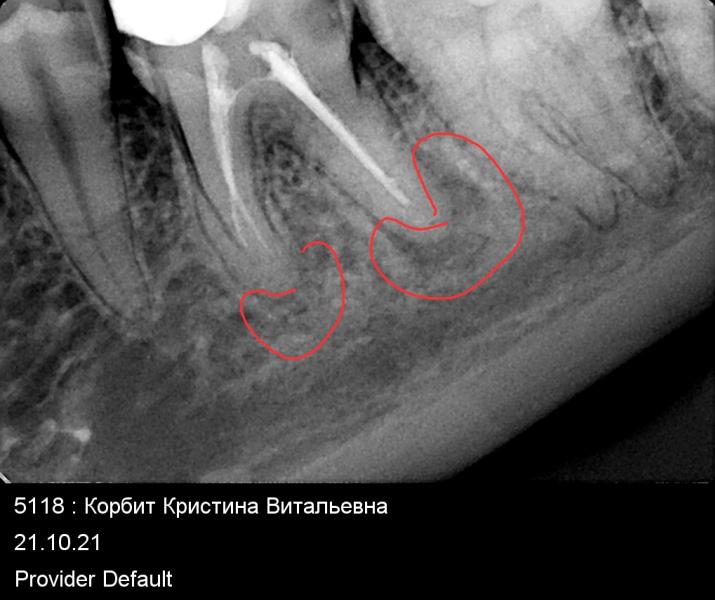

Девочки,хочу услышать мнения остальных,кроме своего и врача)во время Б откололась половина запломбированного ранее зуба,нерв удален,каналы запломбированы.сейчас начал иногда секундно стрелять.сделала снимок: под пломбой образовался "гнойный канал".врач предлагает либо удалить,либо ± пол года бороться за зуб,снял пломбу с половины зуба и чистить и т.д.,смотреть динамику раз в 1,5/2 месяца.но гарантии на него она не даст,в отличии от моих других зубов .чтоб вы решили?

А причем тут прочистка канала?канал ранее прочистили и запломбировали.на снимке канал белый,а гнойный карман ниже)

Пытаться перелечить, прогноз неплохой по этому снимку. Через полгода оценить динамику и думать что дальше делать. Удаление - это последнее, ни один имплант не сравнится с собственным зубом.